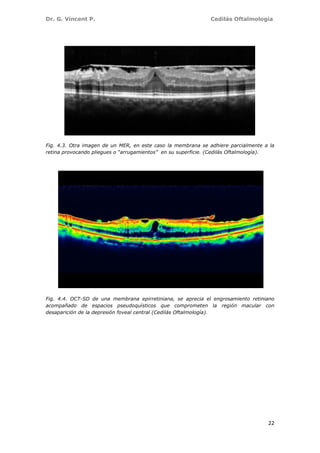

La imagen típica de una membrana epirretiniana en la OCT es la de una

micras (Figs. 4.3, 4.4 y 4.5).

Fig. 4.3. Otra imagen de un MER, en este caso la membrana se adhiere parcialmente a la

retina provocando pliegues o “arrugamientos” en su superficie. (Cedilás Oftalmología).

Fig. 4.4. OCT-SD de una membrana epirretiniana, se aprecia el engrosamiento retiniano

desaparición de la depresión foveal central (Cedilás Oftalmología).